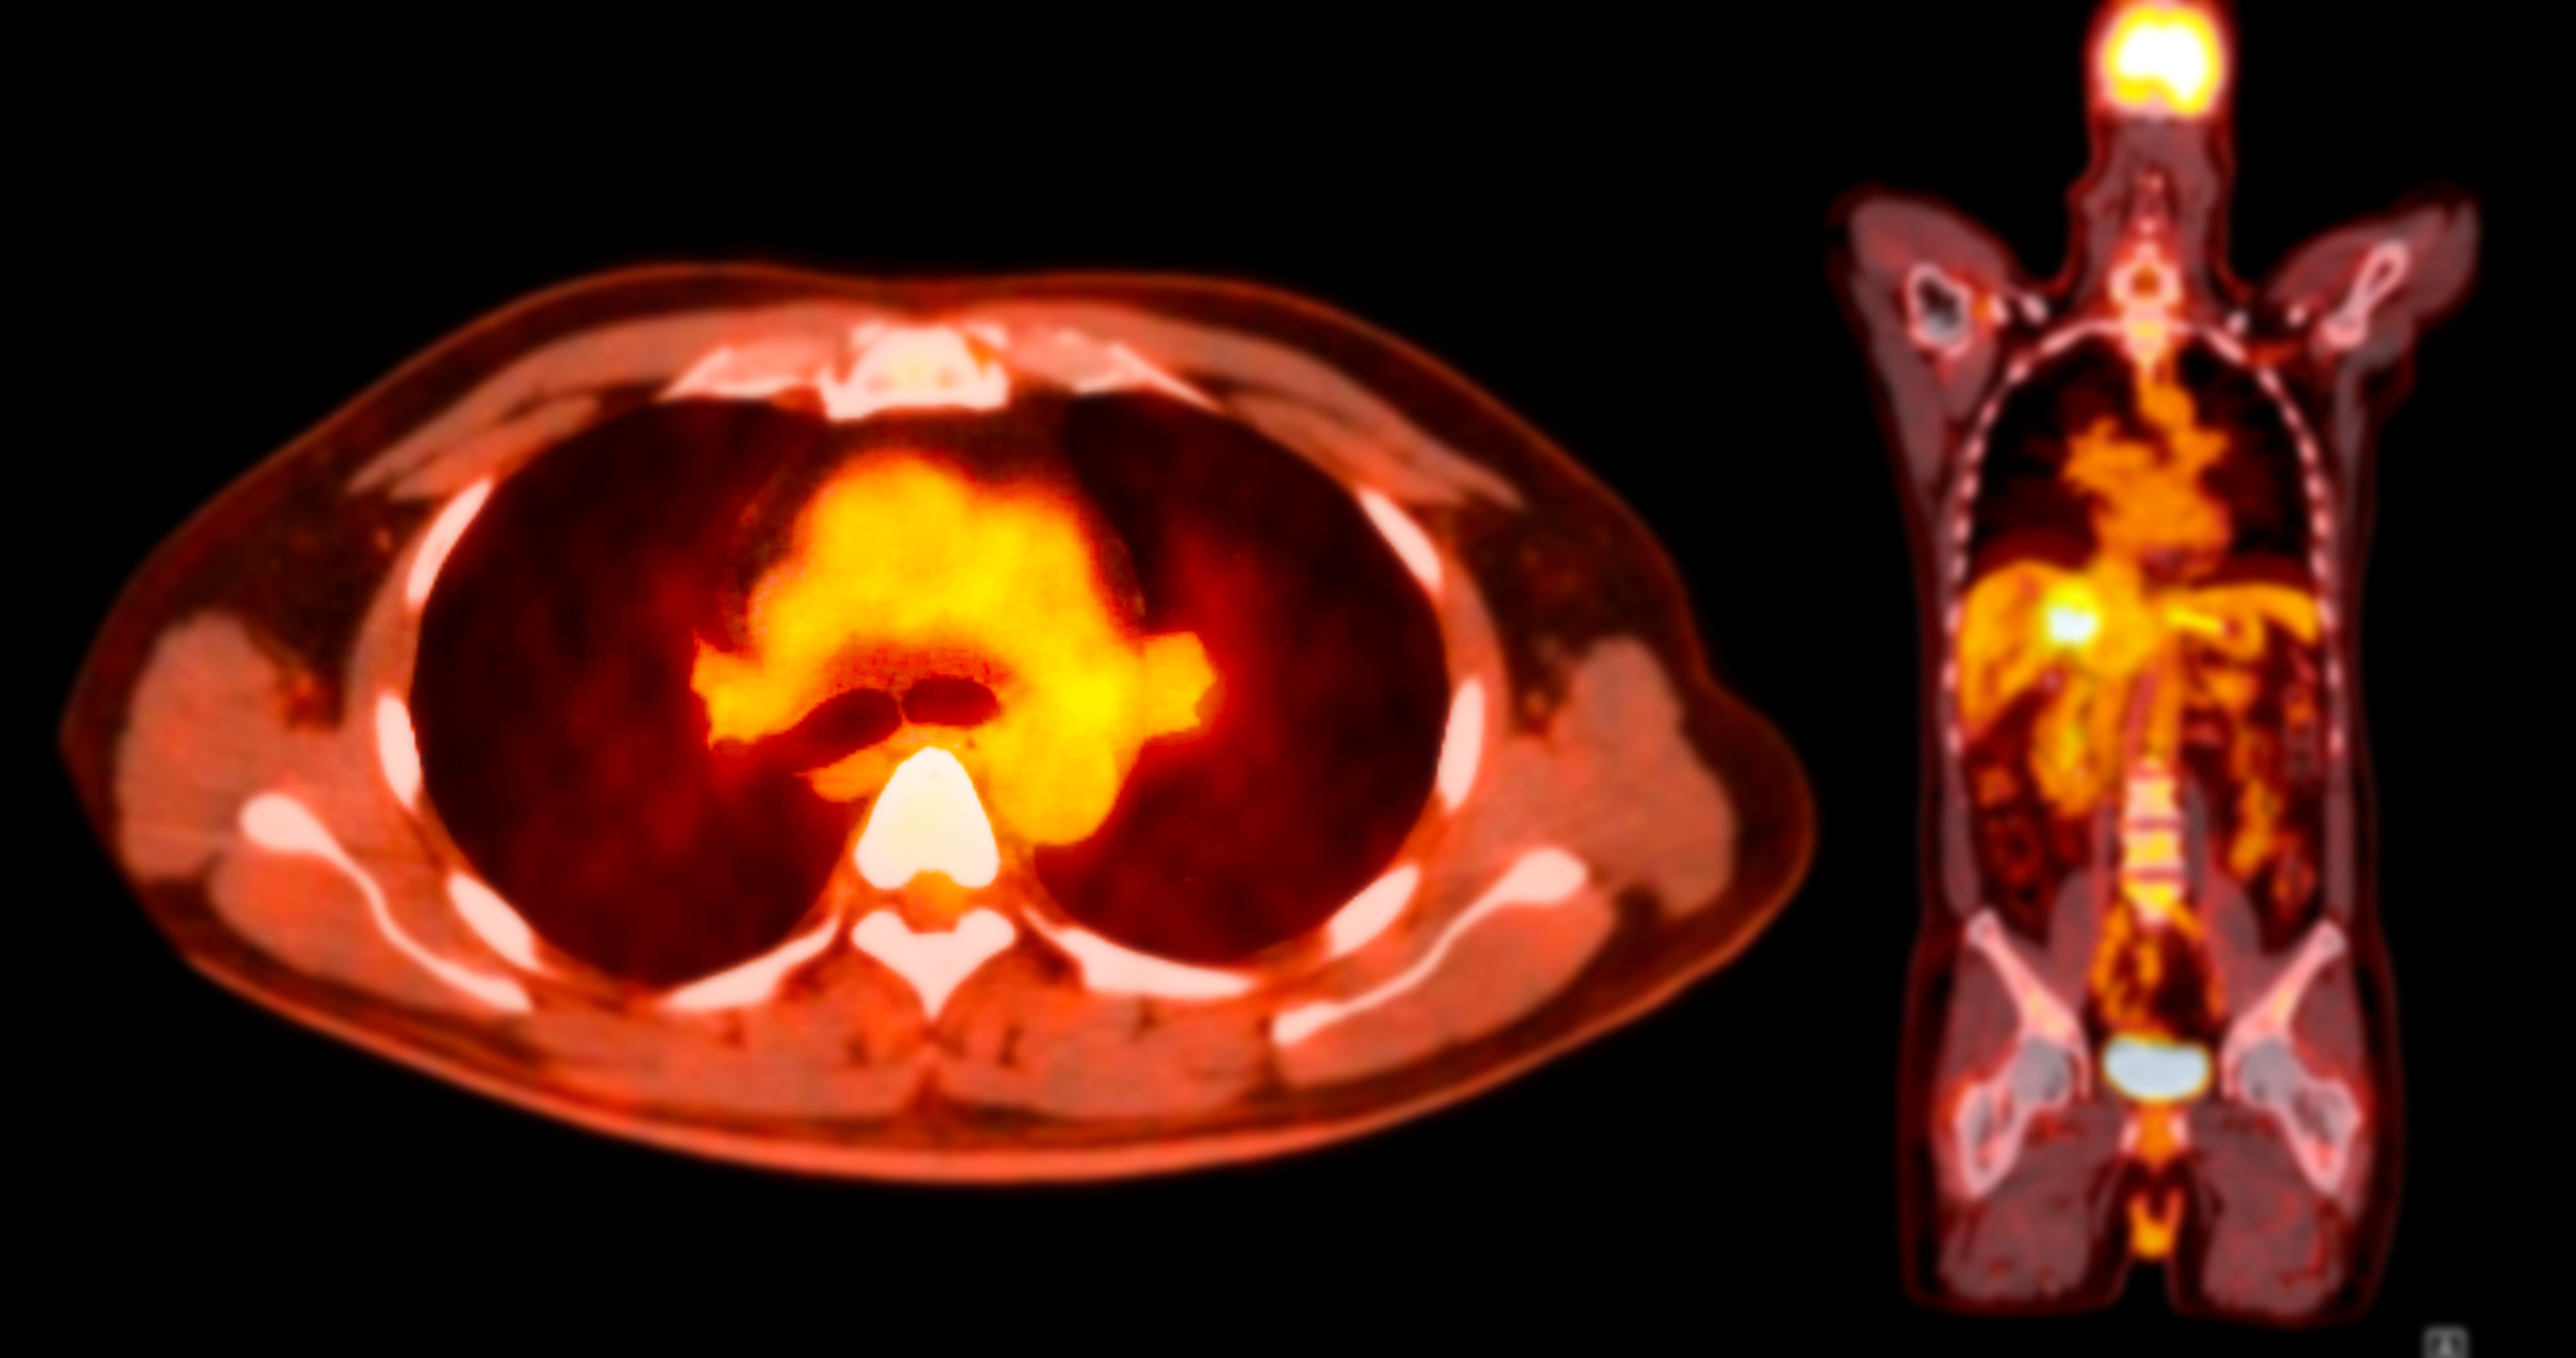

Medical imaging plays a pivotal role in Hematology clinical trials, especially when precision, speed, and consistency are critical to success. This webinar walks through the imaging lifecycle, from protocol design to final deliverables, highlighting how thoughtful planning and execution can accelerate startup timelines and ensure high-quality reads. Join us to explore how imaging workflows can be optimized to support hematologic endpoints and compressed delivery schedules.